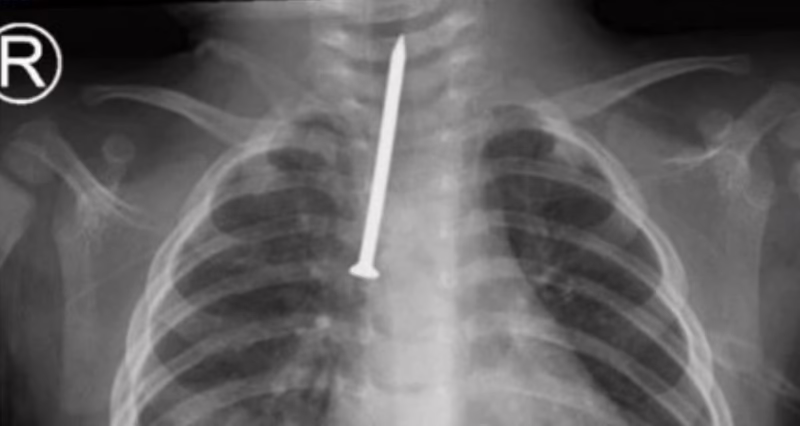

أنقذ فريق طبي في مدينة الملك سعود الطبية حياة طفل رضيع يبلغ من العمر 8 أشهر، بعد إجراء عملية دقيقة لاستخراج مسمار من مجرى التنفس.

وأجرى الفريق عملية تنظير صلب للقصبة الهوائية ومجرى التنفس، حيث نجح خلالها في استخراج مسمار بطول 5 سنتيمترات قد استنشقه بشكل مفاجئ، ما أدى إلى دخوله في مجرى الهواء الرئيسي وتسببه بحالة صحية حرجة.

وأفاد رئيس قسم جراحة الصدر ورئيس الفريق الجراحي، محمد العمصي، بأن الطفل كان يعاني من صعوبة حادة في التنفس، ما استدعى التدخل العاجل لإنقاذ حياته، وتفادي مضاعفات خطيرة نتيجة وجود جسم غريب بهذا الحجم في القصبة الهوائية، حيث تم نقل المريض بشكل عاجل إلى غرفة العمليات وعمل المنظار اللازم للقصبة الهوائية ومجرى التنفس، وتم من خلاله استخراج المسمار.